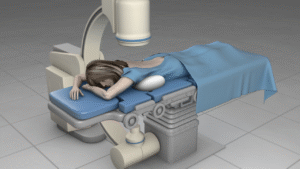

- Minimally invasive procedures

- Neuromodulation